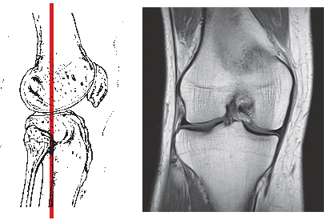

Задний вид на крестообразные и боковые связки, а также мениск колена.

Магнитно-резонансное изображение крестообразных и боковых связок с мениском колена.